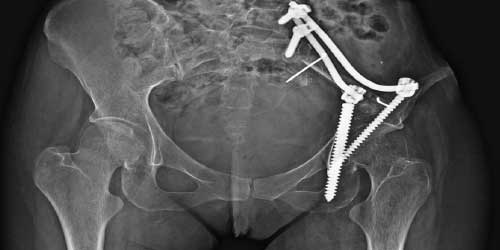

Omurilik basısına neden olan tümör dokusunun ortadan kaldırılması ve omurganın sabitlenmesi: Özellikle malign karakterdeki tümörler omurilik basısına neden olarak kısmı ya da tam felçe neden olabilir. Bu durumda basıyı ortadan kaldırmak için omuriliğin etrafı boşaltılır (seperasyon cerrahisi) ve etkilenen omurgayı sabitlemek için vidalama yöntemi (enstrümentasyon) uygulanır.